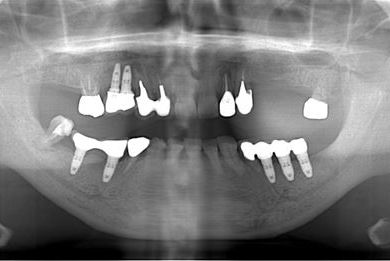

インプラントの症例写真 IMPLANT

骨再生インプラント治療

| 性別/年齢 | 男性 / 58歳 | ||||||||||||||||||||||||||||||||

| 主訴 | ブリッジがだめになったため、現在は部分入れ歯を使用しているが、インプラント治療を検討している。 | ||||||||||||||||||||||||||||||||

| 治療方針 | 左上奥の欠損部分をインプラント治療にて、機能的・審美的回復を行う。 | ||||||||||||||||||||||||||||||||

| 治療内容 | インプラント3本(GBR)、ハイブリッドセラミッククラウン3本 | ||||||||||||||||||||||||||||||||

| 総治療費 | 791,520円 | ||||||||||||||||||||||||||||||||

| 治療期間 | 10ヶ月 |